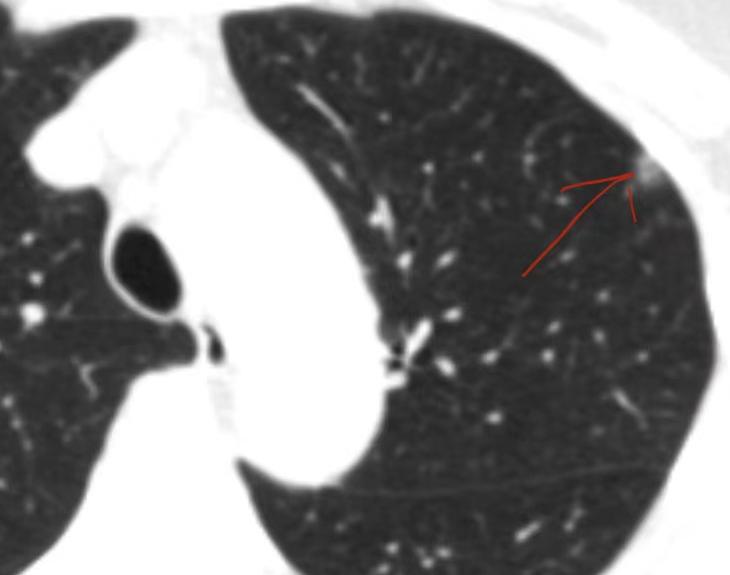

50岁女性双肺多发结节,随访发现变化急就医,术后终安心!山东的杨女士,半年前体检